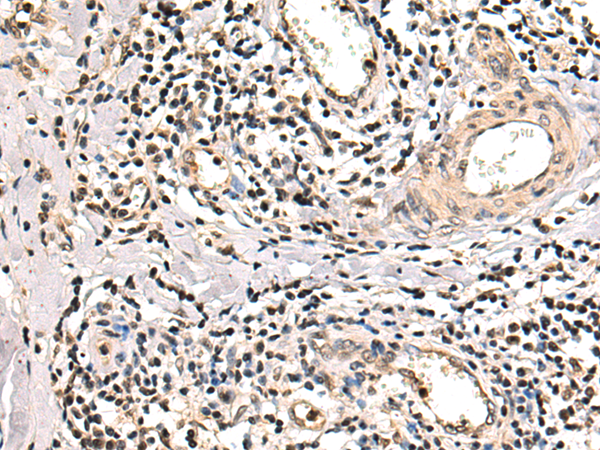

分类: 科研抗体货号: P00620别名: OI6; OI12; PEDF; EPC-1; PIG35应用: WB,IHC反应种属: Human, Mouse